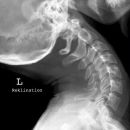

HWS seitlich

- 2) Fehlhaltung z.B. Kyphose (z.B. im Sinne einer traumatischen Kyphose)?

- Physiologisches Treppenphänomen der kindlichen HWS, das eine Dislokation vortäuschen kann (Pseudoluxation) - v.a. bei Kindern unter 8 Jahren Höhe C2/3 und/oder C3/4

- Bei Kindern kann der vordere Atlasbogen die Densspitze bei reklination überragen